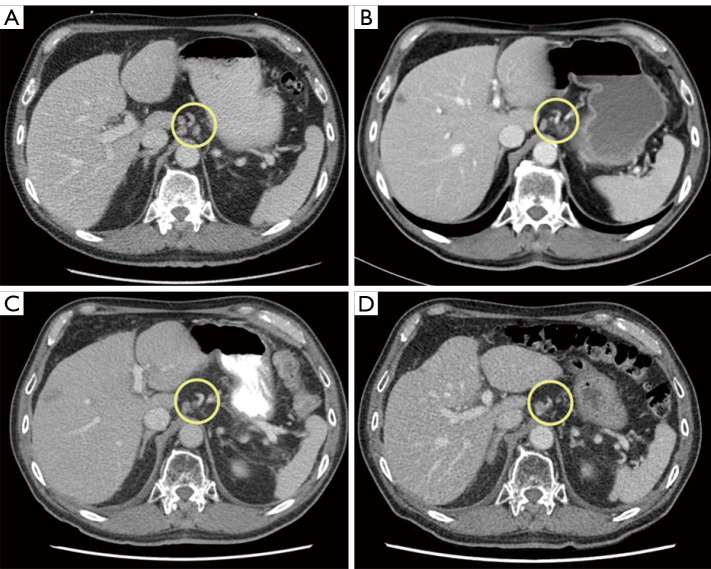

Case description: A 75-year-old gentleman with preexisting multivessel CAD was diagnosed with metastatic gastroesophageal junction (GEJ) squamous cell carcinoma (SCC) after presenting to medical attention with a 2-month history of worsening chest pain in addition to progressive dysphagia associated with weight loss. Following initial treatment with palliative locoregional radiotherapy to the lower mediastinum, GEJ, and upper abdomen, the decision was made to proceed with palliative systemic therapy. Considering his significant cardiac history, 5-FU was replaced with raltitrexed and combined with carboplatin and pembrolizumab. After a total of 10 months of treatment, the patient presented to hospital with recurrent chest pain and was diagnosed with a non-ST-elevation myocardial infarction (NSTEMI). Despite radiographic evidence of stability of his malignancy on systemic therapy, he was not considered to be a candidate for cardiac intervention. He was thus transitioned to a comfort-focused care approach and passed away shortly thereafter, with the cause of death being acute coronary syndrome.